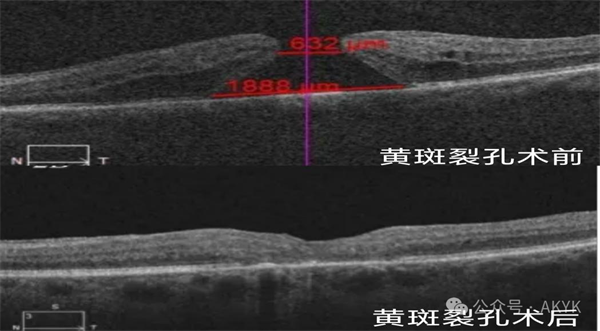

復雜黃斑裂孔修復術:修補裂孔提升視力,降低致盲率。